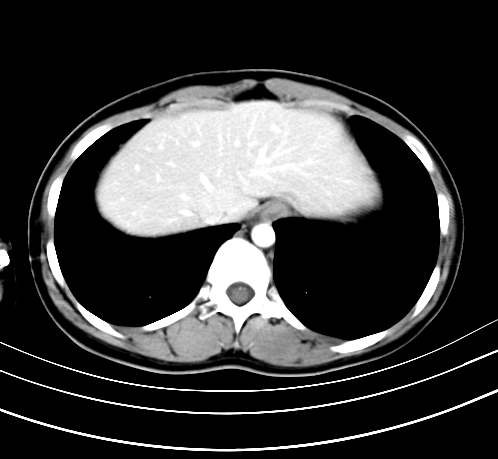

动脉期